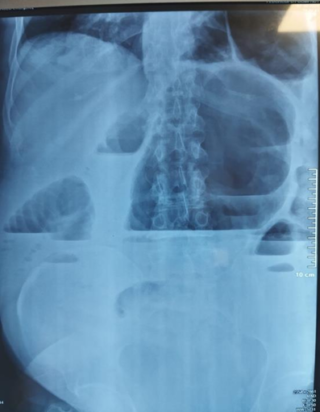

Radiographie de l’abdomen (ASP) : L’examen a mis en évidence des niveaux hydro-aériques mixtes, intéressant à la fois le côlon et l’intestin grêle.

Figure 1 : ASP montrant des niveaux hydro-aériques mixtes. -